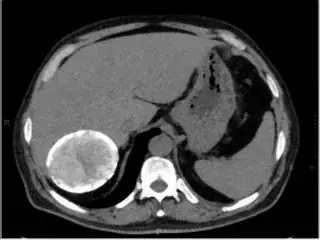

Below I apply two successive morphological openings to the image using a 3x3 circular kernel, and then apply k-means clustering to the gray levels. From your sample images and some I found on the internet, I decided to set k = 4. If you are using high-resolution images, first downsample them to dimensions ~400-600. Otherwise the morphological operation may not have a significant effect, and the k-means will be slow.

Below are some of the opened and segmented images. Of course there's more to be done in terms of

- separating out the liver region

- generalizing this to a large dataset

but hope this is at least a starting point.

You might be able to narrow down the region or interest by filtering out the darkest and the lightest regions from the segmented image. For this, use the k-means cluster centers, check for the extreme values (max and min) and remove the corresponding k values from the labeled image. Then you can look for large structures to the left of the result image. Worst case, you might get a hole on the left side when the extreme region filtering goes wrong. I've updated the code and results.